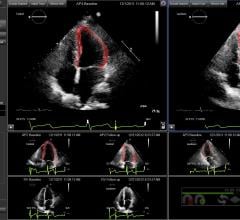

ScImage Inc. recently announced West Virginia University Health System has partnered with ScImage to utilize ScImage’s PICOM365 Enterprise PACS (picture archiving and communication system) throughout the eight WVU Medicine hospitals. The high-security, cloud-based PICOM365 will deliver cardiovascular image management, viewing and reporting capabilities for seamless workflow throughout the health system.